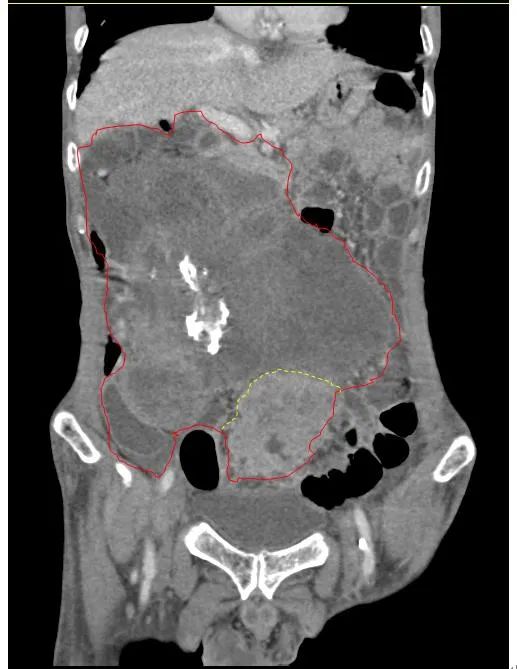

患者王大爺,男,72歲,發(fā)現(xiàn)腹腔腫物10余年,近兩年來患者雙下肢乏力、貧血,依靠間斷輸血維持著正常生活,出現(xiàn)頭昏,行動困難,腹部疼痛及便血慕名來我院就診。入院后查體評估患者年齡大,體質(zhì)差,嚴(yán)重貧血,肺部感染及腸梗阻征象,腹部增強CT檢查提示腹膜后巨大腫瘤,長徑超過30厘米,占據(jù)大部分腹腔,并可能存在雙原發(fā)腫瘤。

苗滿園腫瘤外科團隊在麻醉科/手術(shù)室的緊密配合下為該患者進行手術(shù),術(shù)中發(fā)現(xiàn)腫瘤巨大,幾乎占據(jù)了整個腹腔,從左側(cè)向右腹腔延伸,向上將肝、腎擠向膈下,向左將胃及小腸擠向左上腹,向下深達盆腔內(nèi),包繞下腔靜脈、腸系膜上動脈等大血管及輸尿管,回盲部及回腸也受侵犯。手術(shù)難度巨大,風(fēng)險極高。團隊?wèi){借著高超的手術(shù)技能和精準(zhǔn)的手術(shù)預(yù)案沉著應(yīng)對,迎難而上,應(yīng)用高頻電刀、超聲刀、切割縫合器等先進設(shè)備,耗時近5小時為患者切除了巨大腹腔腫瘤,并聯(lián)合右半結(jié)腸切除,術(shù)中出血僅50ml。術(shù)后病理為腹膜后巨大平滑肌瘤+回腸腺癌。